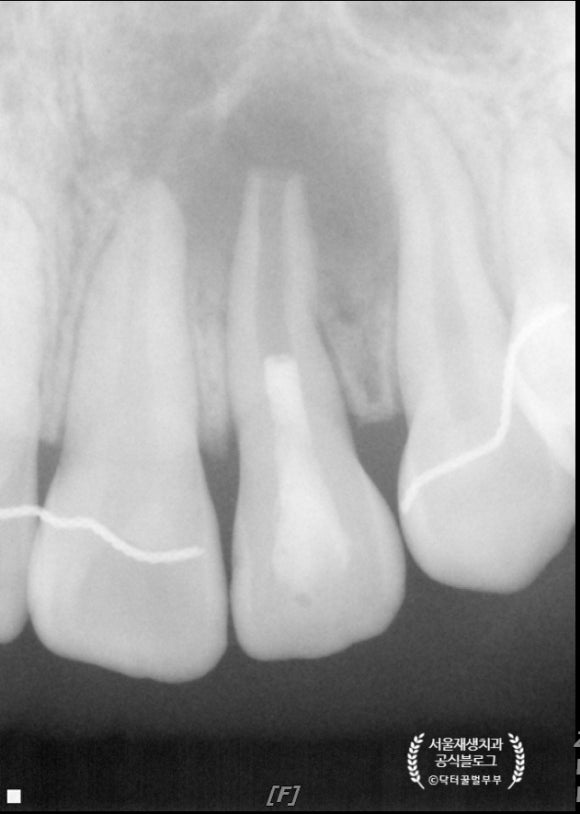

세 달 후에 왔습니다.

병소가 확연히 줄어든 것이 보입니다.

뿌리도 조금 더 두꺼워졌군요.

4개월 후에 왔습니다.

햇살 무늬처럼 가장자리에서부터 뼈가 재생되는 것, 이제는 보이시지요?^^